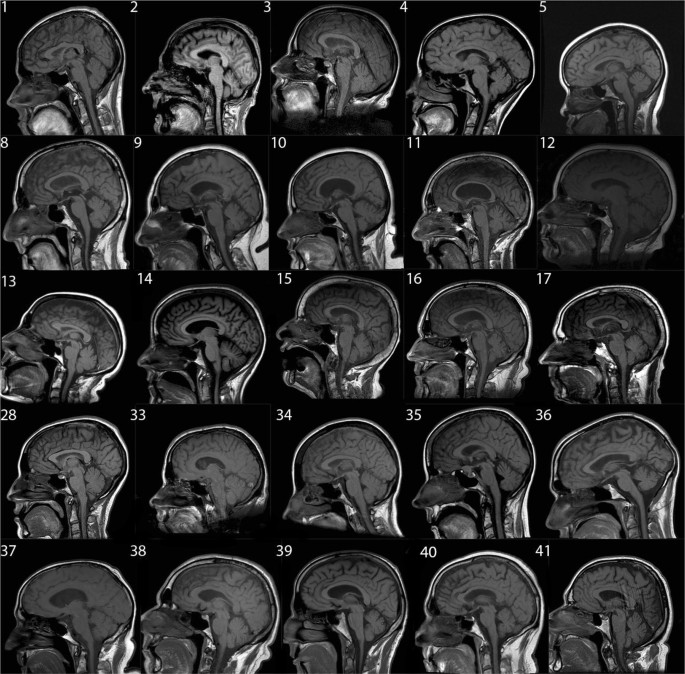

Patient had brain MRIs for reasons either directly related to their disease or related to something else such as headache or to rule out stroke. All patients underwent 1.5 T brain MRIs. Abnormalities of the tongue were observed in 11/33 of the patients. However, in only one patient the tongue was reported as abnormal in the radiology report. Representative MRI cases are shown in the Fig. 1.

Representative sagittal brain T1 MRIs. Patients’ diagnosis, description and tongue findings are in the table. Patients 37 through 41 are normal controls

All patients had MRI after onset of symptoms and diagnosis. Four of the six Pompe patients had abnormal tongue signal and 2/6 had tongue atrophy. However, only one of those patients had dysphagia and none had dysarthria. Length of disease did not seem to play a role in this small cohort. Tongue signal abnormalities or “bright tongue” was most striking in Pompe patients in comparison with the rest of the patients studied.